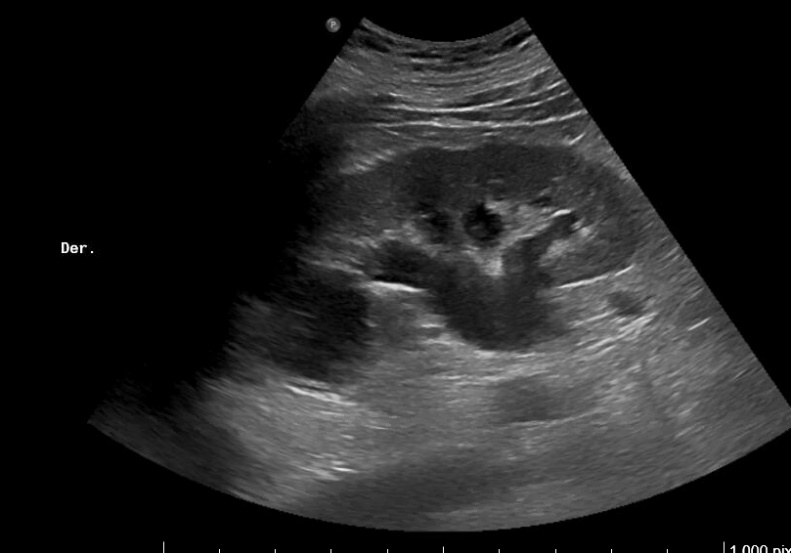

Imágenes 2 y 3. Riñón izquierdo: hidronefrosis grado II. Disminución del grosor cortical. Tamaño 11.5 cm.